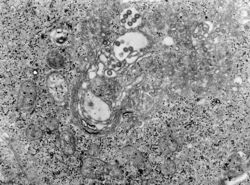

主要病理改變是血管內膜的損害導致紅細胞和血漿外漏。腦、肝和心臟有充血、水腫、局灶性壞死和出血。在單核吞噬細胞內有特異的病毒抗原。